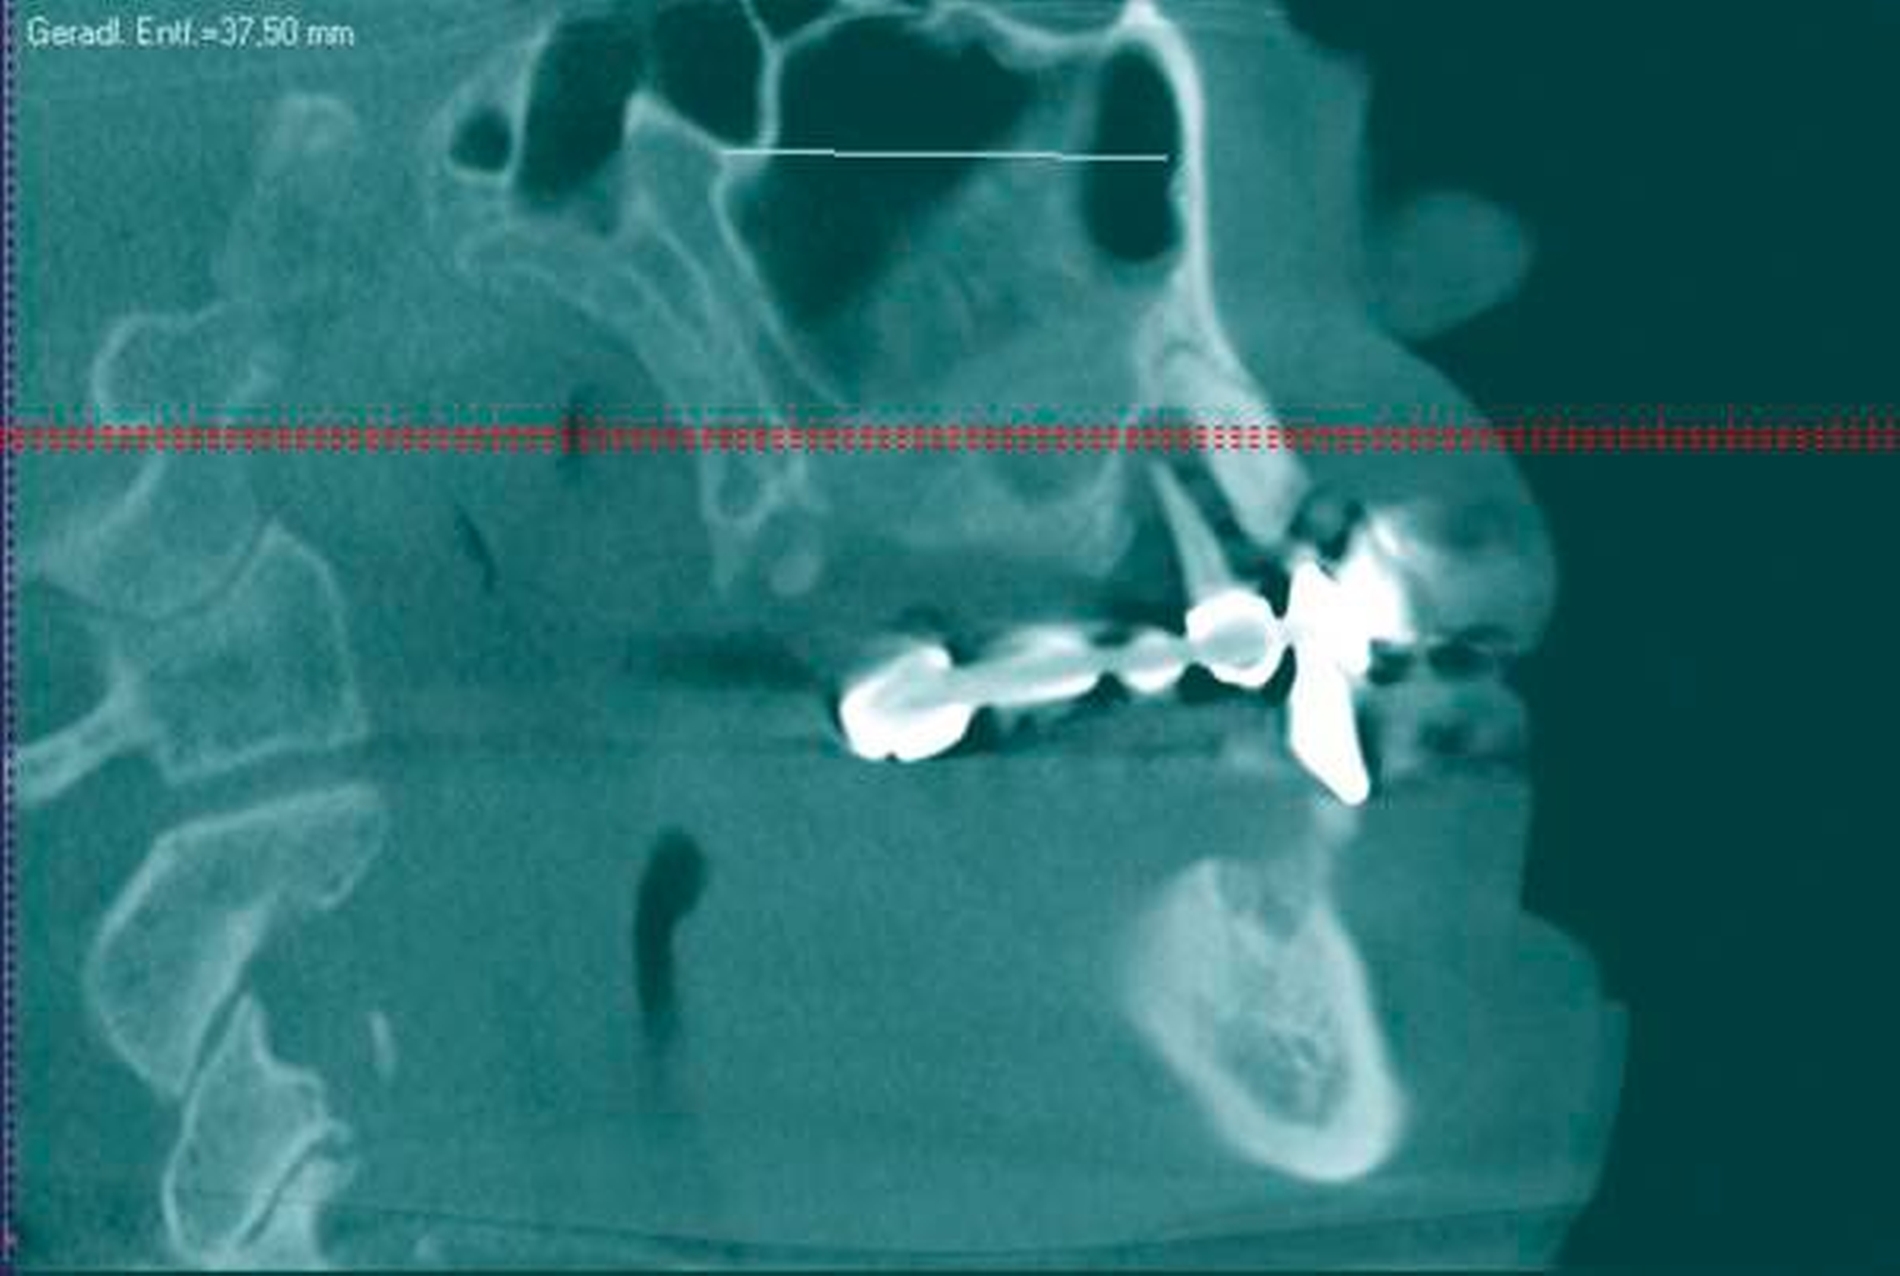

In der durchgeführten radiologischen Diagnostik zeigten sich ausgeprägte Parodontopathien mit Verdacht auf eine BRONJ bei gut begrenzter radiologischer Aufhellung mit Kieferhöhlenbeteilung (Abbildungen 3 bis 5). Unter der Verdachtsdiagnose einer BRONJ wurde somit die Indikation zur Zahnsanierung mit Exzision der pathologischen Veränderung im Oberkiefer gestellt. Nach Entfernung der gelockerten Brücke zusammen mit den die Brücke tragenden Zähnen zeigten sich große Mengen harten, anhaftenden Gewebes (Abbildung 6); der unter dem Befund liegende Knochen stellte sich klinisch als vital und ohne Anzeichen einer Nekrose dar.